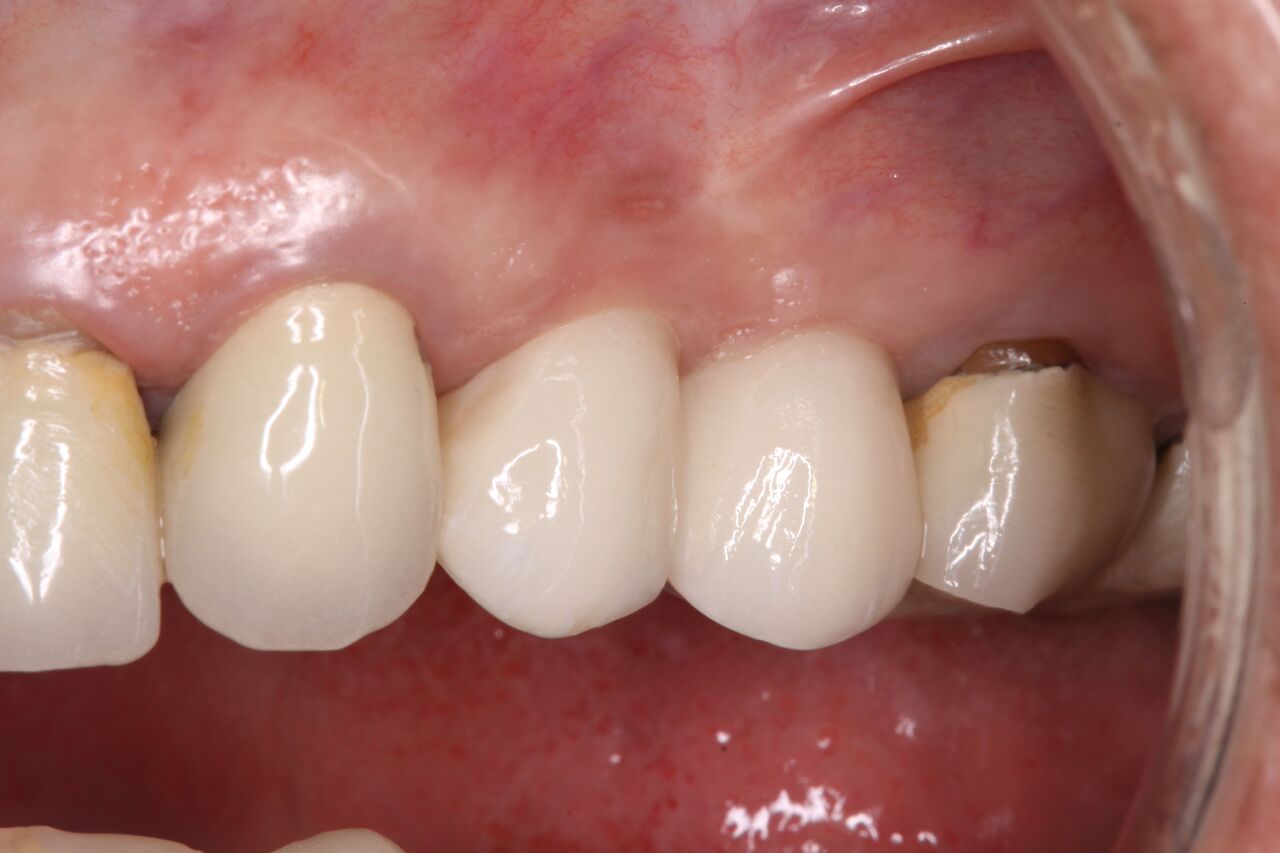

(15.) Clinical view of final individual crowns on Nos. 12 and 13.

Figure 15

The patient was prescribed antibiotics and analgesics and instructed in postoperative care particular to immediately provisionally restored implants. At 6 months, integration was confirmed (Figure 14) and the patient returned to her dentist for restoration. The implants were restored with individual cement-retained crowns with a platform shift for No. 12 restoration from the 6-mm diameter of the implant to a 5-mm diameter of the final restoration (Figure 15 and Figure 16).